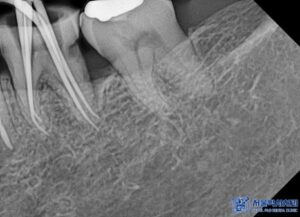

먼저 전체적인 검진 결과,

왼쪽 아래 큰 어금니 부위에서

금 인레이 아래쪽으로 이차 충치와

염증이 발견되었습니다.

해당 치아는 신경 치료가

필요한 상태였기 때문에

서울박사치과에서는

자연치아 보존을 최우선으로 하는

“MTA 신경치료”를 진행하기로 하였습니다.